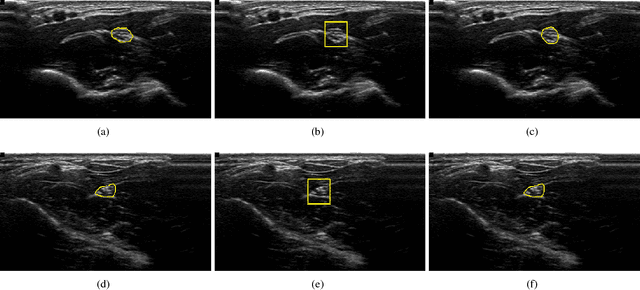

Ultrasound-Guided Regional Anesthesia (UGRA) has been gaining importance in the last few years, offering numerous advantages over alternative methods of nerve localization (neurostimulation or paraesthesia). However, nerve detection is one of the most tasks that anaesthetists can encounter in the UGRA procedure. Computer aided system that can detect automatically region of nerve, would help practitioner to concentrate more in anaesthetic delivery. In this paper we propose a new method based on deep learning combined with spatiotemporal information to robustly segment the nerve region. The proposed method is based on two phases, localisation and segmentation. The first phase, consists in using convolutional neural network combined with spatial and temporal consistency to detect the nerve zone. The second phase utilises active contour model to delineate the region of interest. Obtained results show the validity of the proposed approach and its robustness.